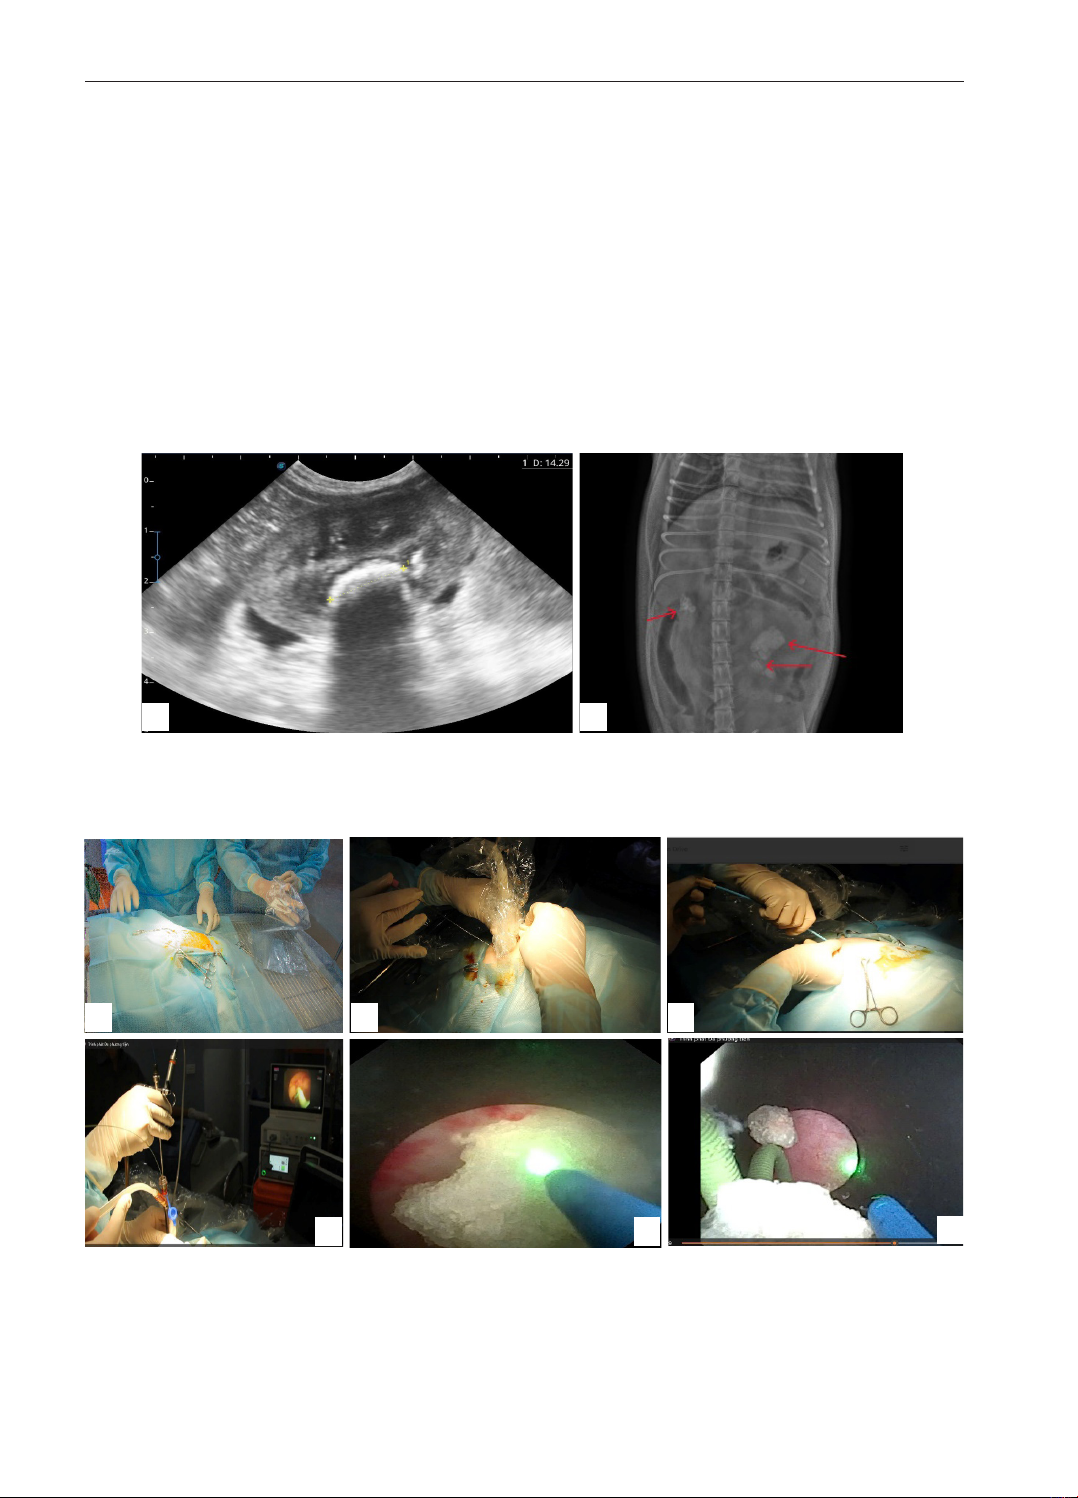

Hình 1. Kt qu chẩn đoán hình nh sỏi bể thận chó poodle bự trước khi tán sỏi

Ghi chú: A: Hình ảnh siêu âm thận trái với hình ảnh sỏi thận đường kính 14,29 mm; B: Hình ảnh chụp

X-quang không chuẩn bị cho thấy các viên sỏi lấp đầy hai bể thận, thận trái giãn to (mũi tên màu đỏ).

A B

Hình 2. Mô t quá trình tán sỏi bể thận trên chó poodle Bự

Ghi chú: A: Chó được gây mê nội khí quản, nằm nghiêng trái; B: Kim chọc dò bể thận dưới hướng dẫn siêu

âm; C: Đặt ống nong tạo đường hầm tán sỏi; D: Thao tác tán sỏi được kiểm soát qua máy soi; E: Tia laser tán

sỏi bể thận; F: Sỏi vụn được hút ra ngoài dưới áp lực nước thông qua đường hầm nhỏ.

A B C

D E F